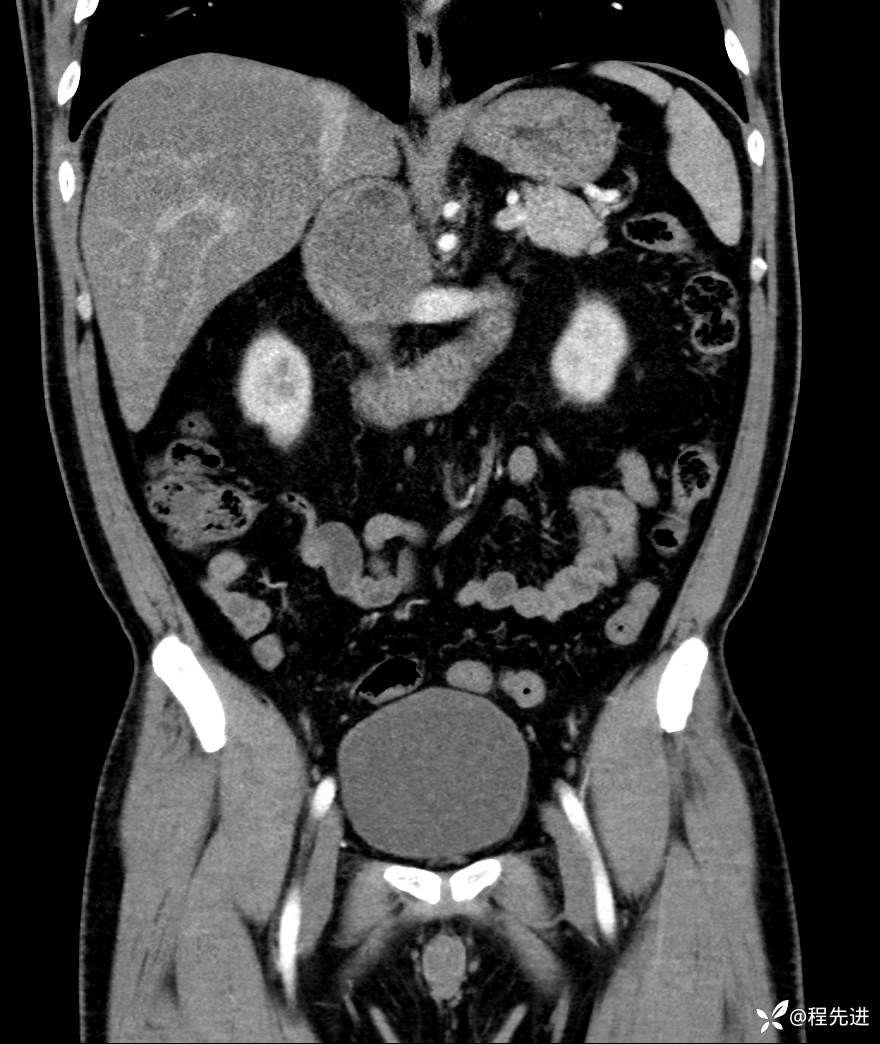

【腹盆】特别精彩病例|发现腹膜后肿物1月余

主诉:发现腹膜后肿物1月余

现病史:患者1月余前查体,行超声检查提示:后腹膜囊实性肿块;慢性胆囊炎伴胆囊内结石;无腹痛腹胀,不伴腹泻发热等;偶感腰背部酸痛。

CT平扫+增强: